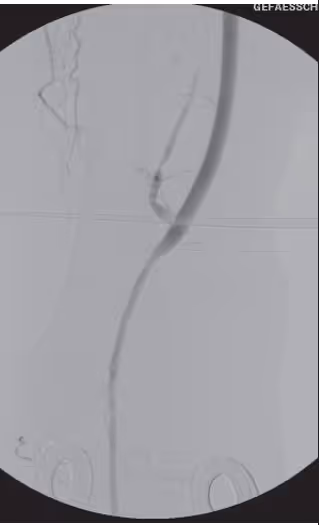

To perform a femoro-popliteal bypass (Dacron or PTFE, 6-8mm)to popliteal artery pars I

Create proximal side-to-end anastomosis in running suture technique

Create distal end-to-end anastomosis in running suture technique

Proximal anastomosis (side-to-end)

Distal anastomosis (end-to-end)